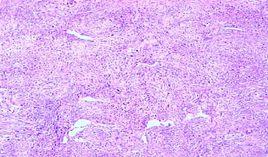

卵巢纖維組織來源腫瘤

卵巢纖維組織來源腫瘤,英文名:tumor from fibrous tissue of ovaries是卵巢非特異性組織腫瘤之一。纖維組織來源腫瘤在卵巢...

肥大結節纖維組織增生